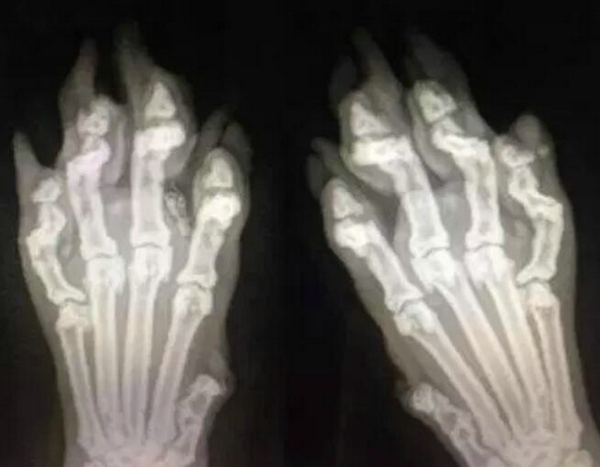

近日微博上这幅猫爪x光,凭着可爱的过分在网络上速火了起来。这幅猫爪x光图看起来那只猫咪一定是肉肉的,小小的爪子,让人看就有想要养只猫的心动!

该图的猫爪的骨头是细细的分开的,难道是骨折了? 不少网友评论说:惨,这是骨折了吗?可爱到骨子里了。

面对这么可爱的猫爪x光图是真否,多数网友表示怀疑。那么我们来看看这幅实际的猫爪x光图,是不是还是那么可爱呢? 奉上猫爪图吸一波~